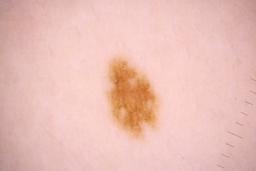

ISIC_8336318

Clinical

| Field | Value |

|---|---|

| age_approx | 40 |

| anatom_site_1 | Trunk |

| anatom_site_2 | Anterior trunk |

| anatom_site_3 | Anterior abdomen |

| clin_size_long_diam_mm | 6.19 |

| diagnosis_1 | Malignant |

| diagnosis_2 | Malignant melanocytic proliferations (Melanoma) |

| diagnosis_3 | Melanoma Invasive |

| diagnosis_4 | Melanoma Invasive, Superficial spreading |

| diagnosis_confirm_type | histopathology |

| image_manipulation | instrument only |

| image_type | TBP tile: close-up |

| lesion_id | IL_5097969 |

| mel_thick_mm | 0.40 |

| patient_id | IP_8989787 |

| sex | male |

| tbp_tile_type | 3D: white |